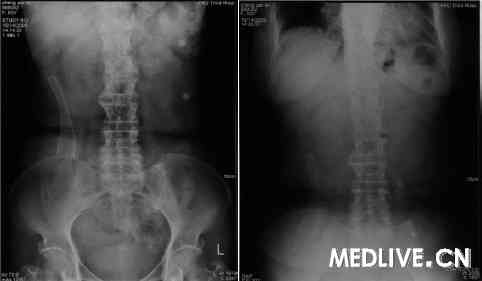

患者于入院后3天行结肠镜下金属支架置入术,结肠镜观察下留置导丝穿过隆起性病变,造影下观察狭窄段长约3~4 cm。经内镜钳道插入金属支架通过狭窄段,在X线以及内镜监视下释放打开支架,位置良好(图4)。 结肠支架置入5天后,肠梗阻完全缓解(图5)。结肠支架置入7天后行腔镜右半结肠根治性切除术,联合腹腔镜

图4 结肠镜下置入金属支架

图5 结肠支架置入后腹部平片(左图:立位,右图:卧位。肠梗阻已经缓解)